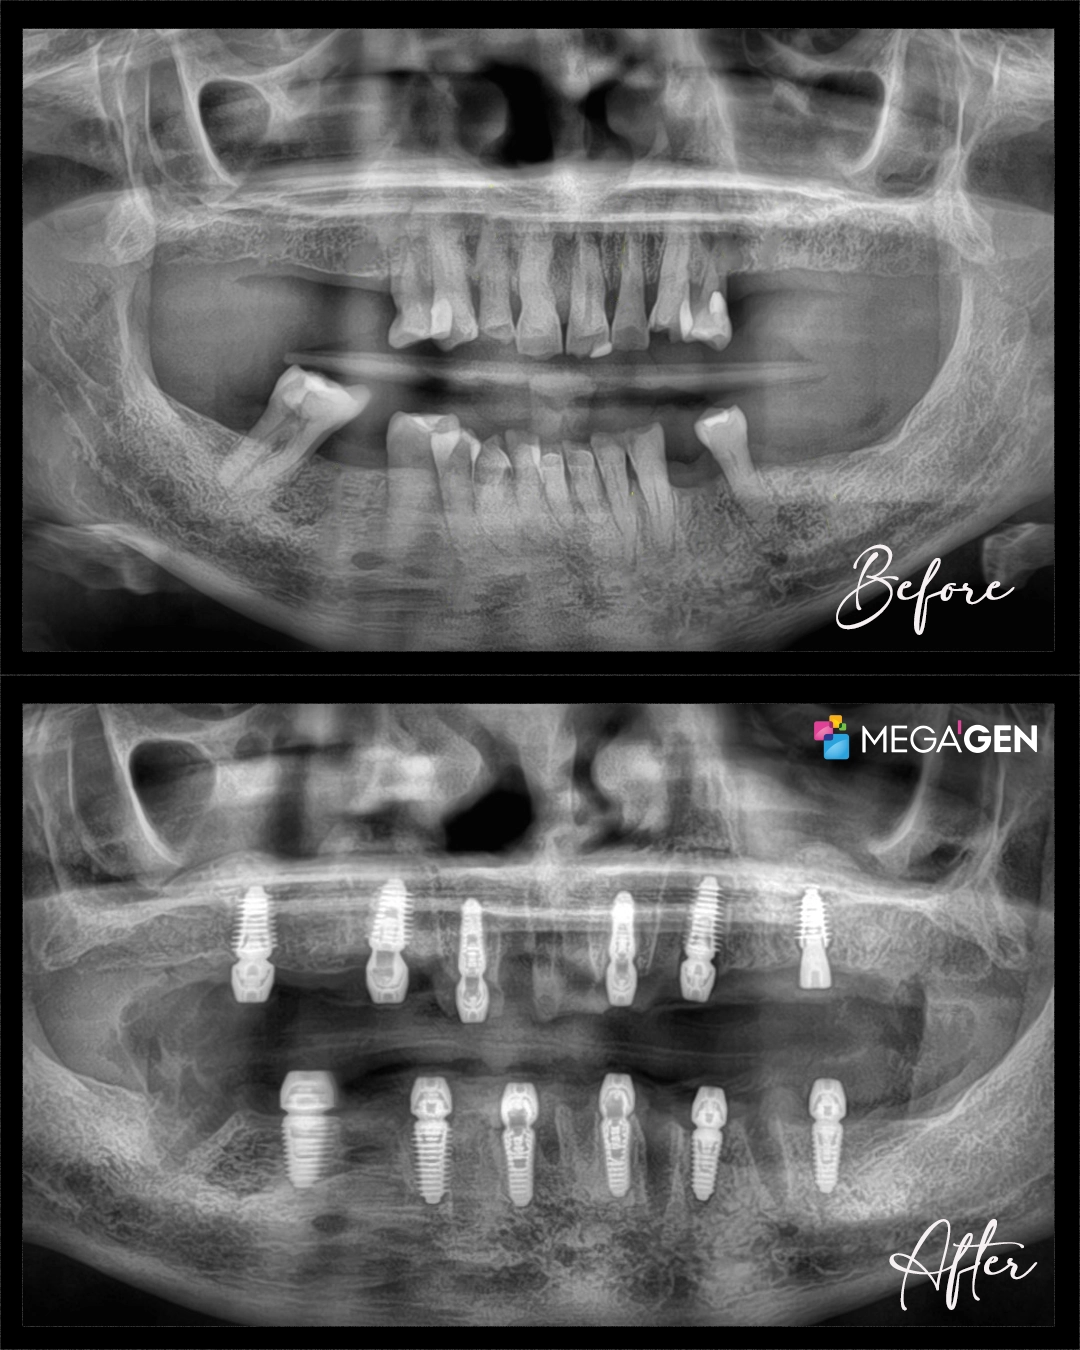

Owen’s first appointment with Dr. Alper began with a comprehensive evaluation. The examination combined clinical assessment with advanced imaging technology, including both 2D panoramic radiographs and 3D CBCT scans. These imaging techniques allow dentists to visualize bone structure, identify infection, and plan implant placement with precision.

The diagnostic images revealed significant periodontal support loss (deterioration of the gums and bone supporting the teeth), advanced tooth mobility, and insufficient bone volume in the upper jaw. These findings indicated that Owen’s remaining teeth could not be saved and that immediate intervention was necessary to prevent further bone loss.

The team determined that Owen’s remaining teeth had poor prognosis and could not be maintained long term. The treatment plan included complete extraction of all teeth, bone augmentation where needed, placement of twelve dental implants, and immediate loading with temporary fixed teeth.

Following extractions, twelve aggressive design dental implants were placed (six in the upper jaw and six in the lower jaw). Aggressive design implants feature enhanced thread patterns that improve initial stability in deteriorated bone. This design proved crucial for Owen’s case, as eleven of the twelve implants achieved primary stability of at least 45 Newton-metre (N·m) of torque.

Placing twelve implants in a single surgery requires significant surgical expertise and careful planning. Dr. Alper strategically positioned six implants in the upper jaw and six in the lower jaw to create stable foundations for the final fixed teeth.

At the end of the six month healing period, Dr. Alper will verify complete osseointegration through clinical examination and radiographs. Once confirmed, the temporary prostheses will be replaced with permanent restorations fabricated from Ivoclar zirconia, providing superior aesthetics and long term durability.